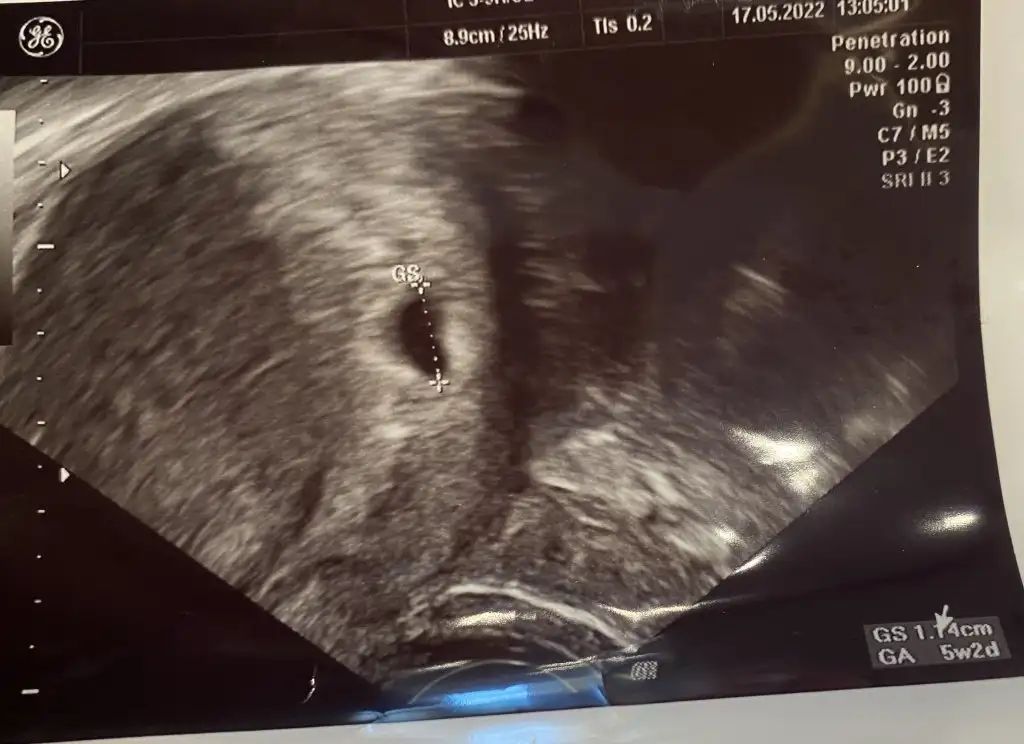

Merhaba bugün transferimin 21. Günü gebelik olarak 5+2 yazıyor doktor her şey normal 2 hafta sonra gel dedi ama bebek gözükmüyor 😢🥺🥺 çok tedirginimm

Eklentiler

• 9E038663-AE78-422A-9E5A-402EBF9D97F7.webp

9E038663-AE78-422A-9E5A-402EBF9D97F7.webp

37,2 KB · Görüntüleme: 59